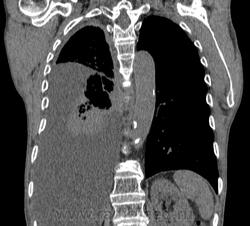

Самое интересное забыла показать- может это 100% навеет на мысль об опухолевом процессе, остеолитическая деструкция позвонка?

Коллеги, распада там нет, это вас медиастинальное окно подвело. В грудине тоже все в порядке. Да и компрессия позвонка "старая".

Небольшое количество увеличенных лимфоузлов, и те - не сказать, чтоб были очень крупными. От эмпиемы до онкологии... Умеренное количество жидкости в перикарде, толщиной слоя до 13-14 мм. При подобной картине не вижу смысла гадать по сжатому лёгкому, пишу так: массивный выпот справа, около 2500 мл, диафрагма оттеснена жидкостью каудально, печень (!!!) смещена каудально и вправо. Легкое справа значительно компрессировано жидкостью, оценка проходимости бронхов и состояния легочной паренхимы (кроме имеющейся эмфиземы) практически невозможна. Необходима пункция плевральной полости справа (цитология, ВК, посев на микрофлору и проч), КТ-контроль после эвакуации жидкости.